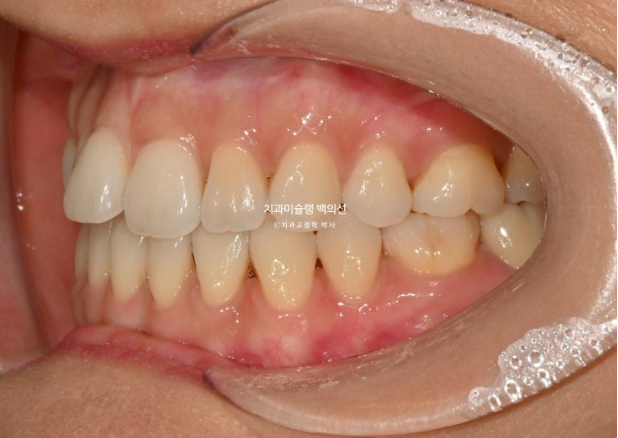

25년 7월부터 9월까지 7개 추가장치를 낀 후 치료를 마무리 했습니다.

25.09

총 치료기간은 6개월이고 재제작은 1회 했습니다.

철사 교정식 유지장치까지 꼼꼼하게 들어갑니다.

이제 전 후 비교 보겠습니다.

25.03~25.09

깔끔해진 미소가 돋보입니다.